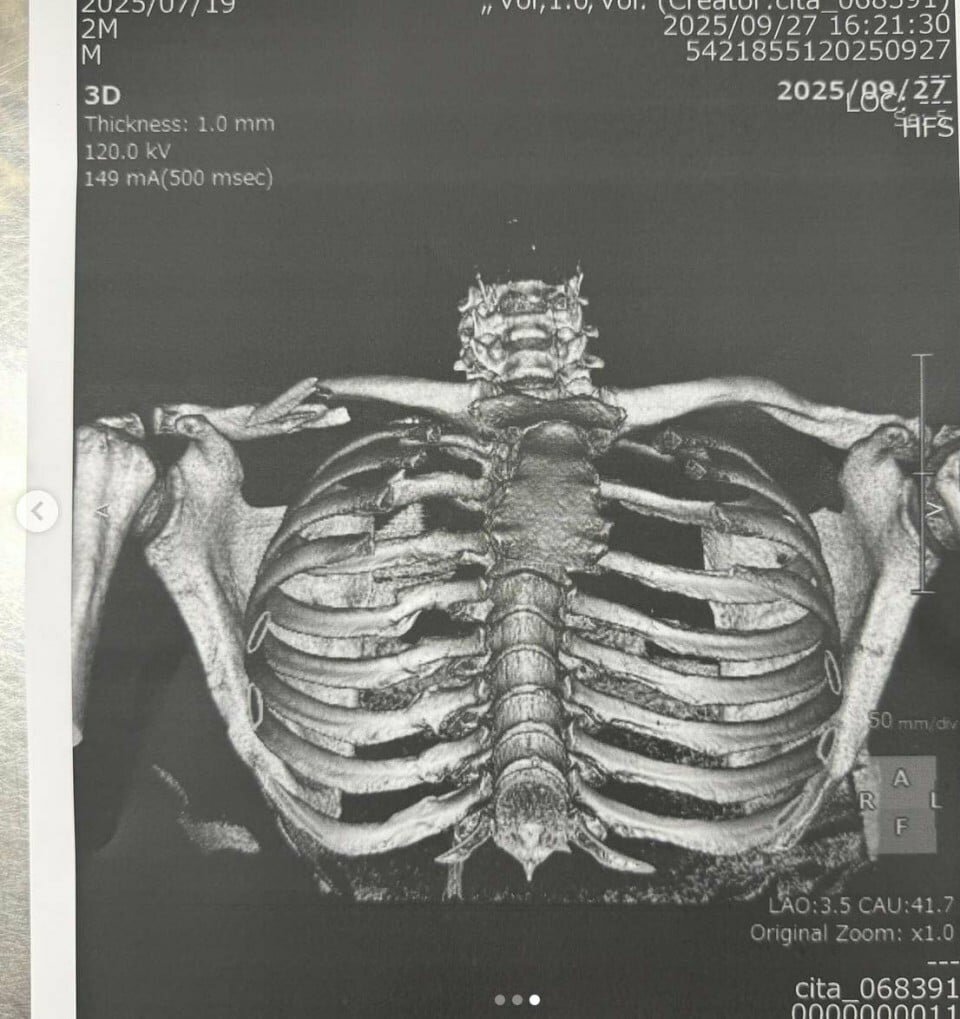

Нет, это не фотография Криминала, другого великого героя нуар-комиксов времён Диаболика, а грудная клетка несчастного Хорхе Мартина, которому вновь не повезло в Мотеги. Действующий чемпион мира, вероятно, пропустит как минимум следующий ГП Индонезии.